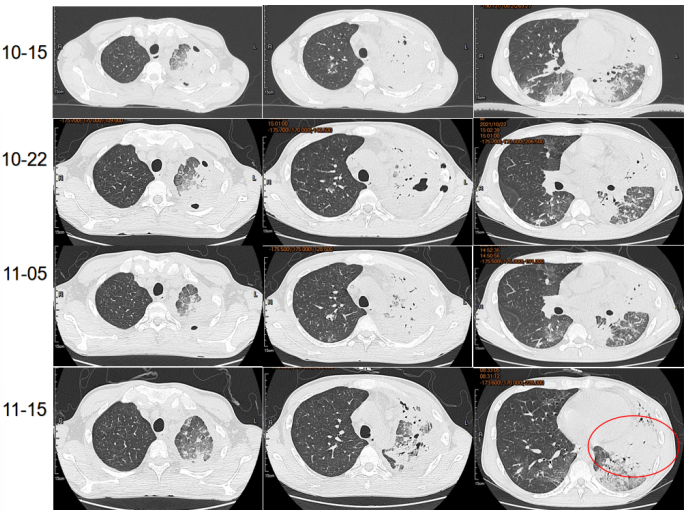

患者在伏立康唑及卡泊芬净联合治疗的情况下,仍然出现影像学进展,考虑治疗效果不佳。从病原学相关因素、宿主相关因素、药物相关因素等三方面进一步明确治疗效果不佳原因。

首先进一步明确病原学,排除其他感染可能,于2021年10月15日予行肺穿刺。

与9月23日相比,11月16日气管镜下见左肺支气管完全通畅,残留少许黏膜粗糙(图15)。

完善嗜肺军团菌尿抗原检测阴性。调整治疗方案,给予左氧氟沙星、哌拉西林他唑巴坦治疗,给予SMZ覆盖肺孢子菌,伏立康唑改为两性霉素B脂质体,同时辅以丙球和粒细胞集落刺激因子治疗(图16)。

改为两性霉素B脂质体后,患者肌酐和尿素氮逐渐升高,后续调整为艾沙康唑治疗,脏器功能有所恢复(图17)。监测艾沙康唑血药浓度均在有效水平。